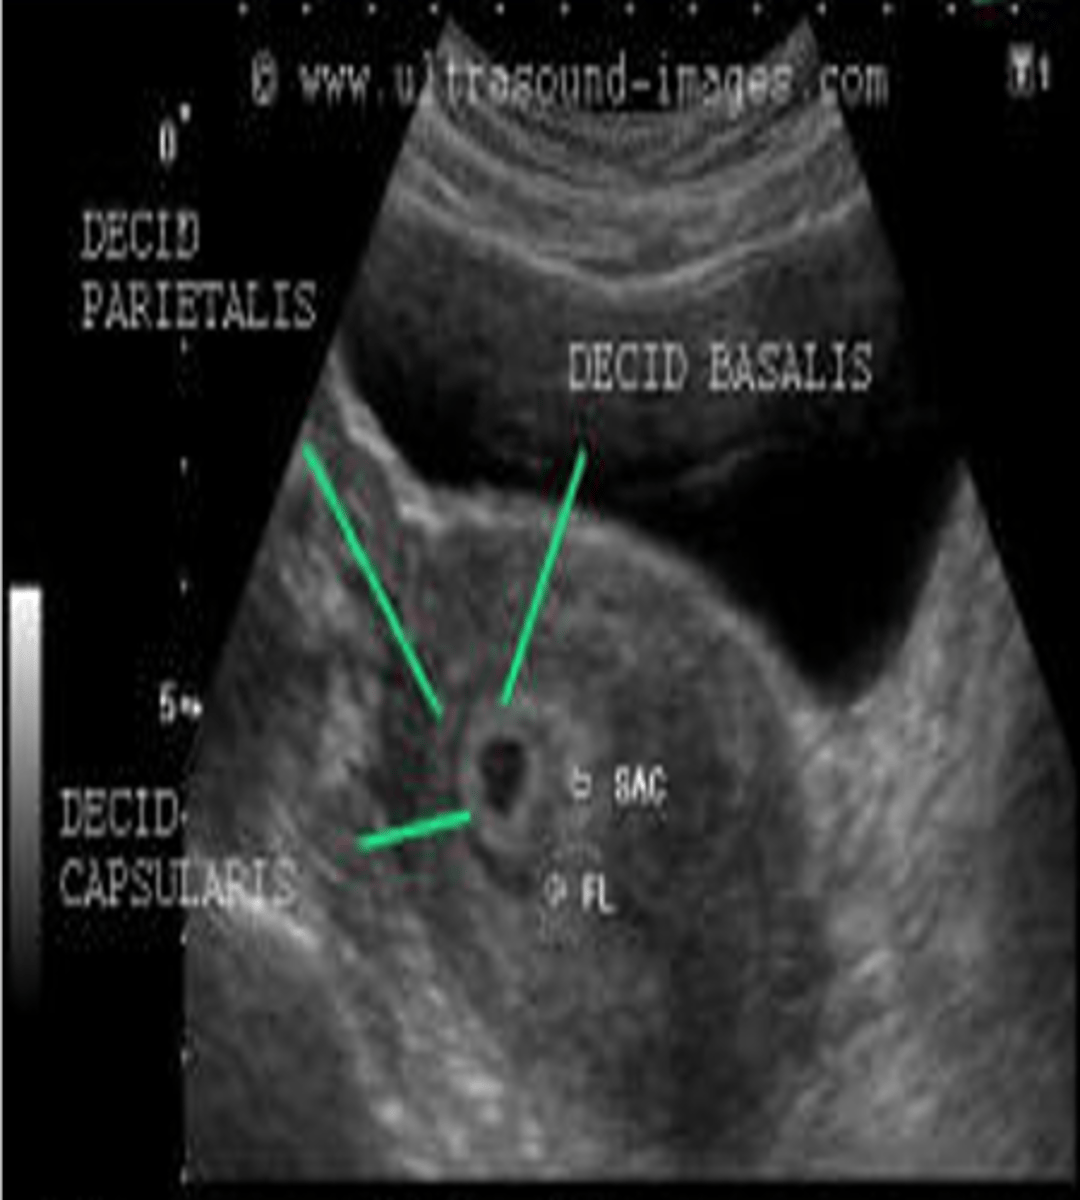

What components can the echogenic ring around the gestational sac be divided into?

decidua basalis

decidua capsularis

double decidual sac sign

The decidua basalis is the ___ on the ___ or burrowing side of the embryo

villi; myometrial (mother's side)

The decidua capsularis is the ___ covering the rest of the ___

villi; developing embryo (baby side)

The double decidual sac sign is an interface between the ___ and the ___

decidua capsularis; endometrium

The double decidual sac sign is a reliable sign of ___

viable gestation

During the 5th week, what is decidua wall thickness?